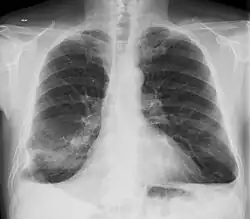

- Pulmón

- La fibrosis pulmonar es una complicación reconocida de la artritis reumatoide[57][58][59] y también puede ser una consecuencia de algunos tratamientos —por ejemplo del metotrexate y leflunomida—.[60] El síndrome de Caplan describe la presencia de nódulos reumatoideos pulmonares en pacientes con artritis reumatoide y exposición al polvo de sílice o carbón. Los derrames pleurales no son raros en el contexto de la artritis reumatoide y obligan a descartar otras posibles causas. Estas alteraciones pulmonares, además de la bronquiolitis obliterante se denominan globalmente enfermedad pulmonar reumatoide, estimándose que al menos una cuarta parte de los pacientes con artritis reumatoide desarrollan afectación pulmonar.[61][62]